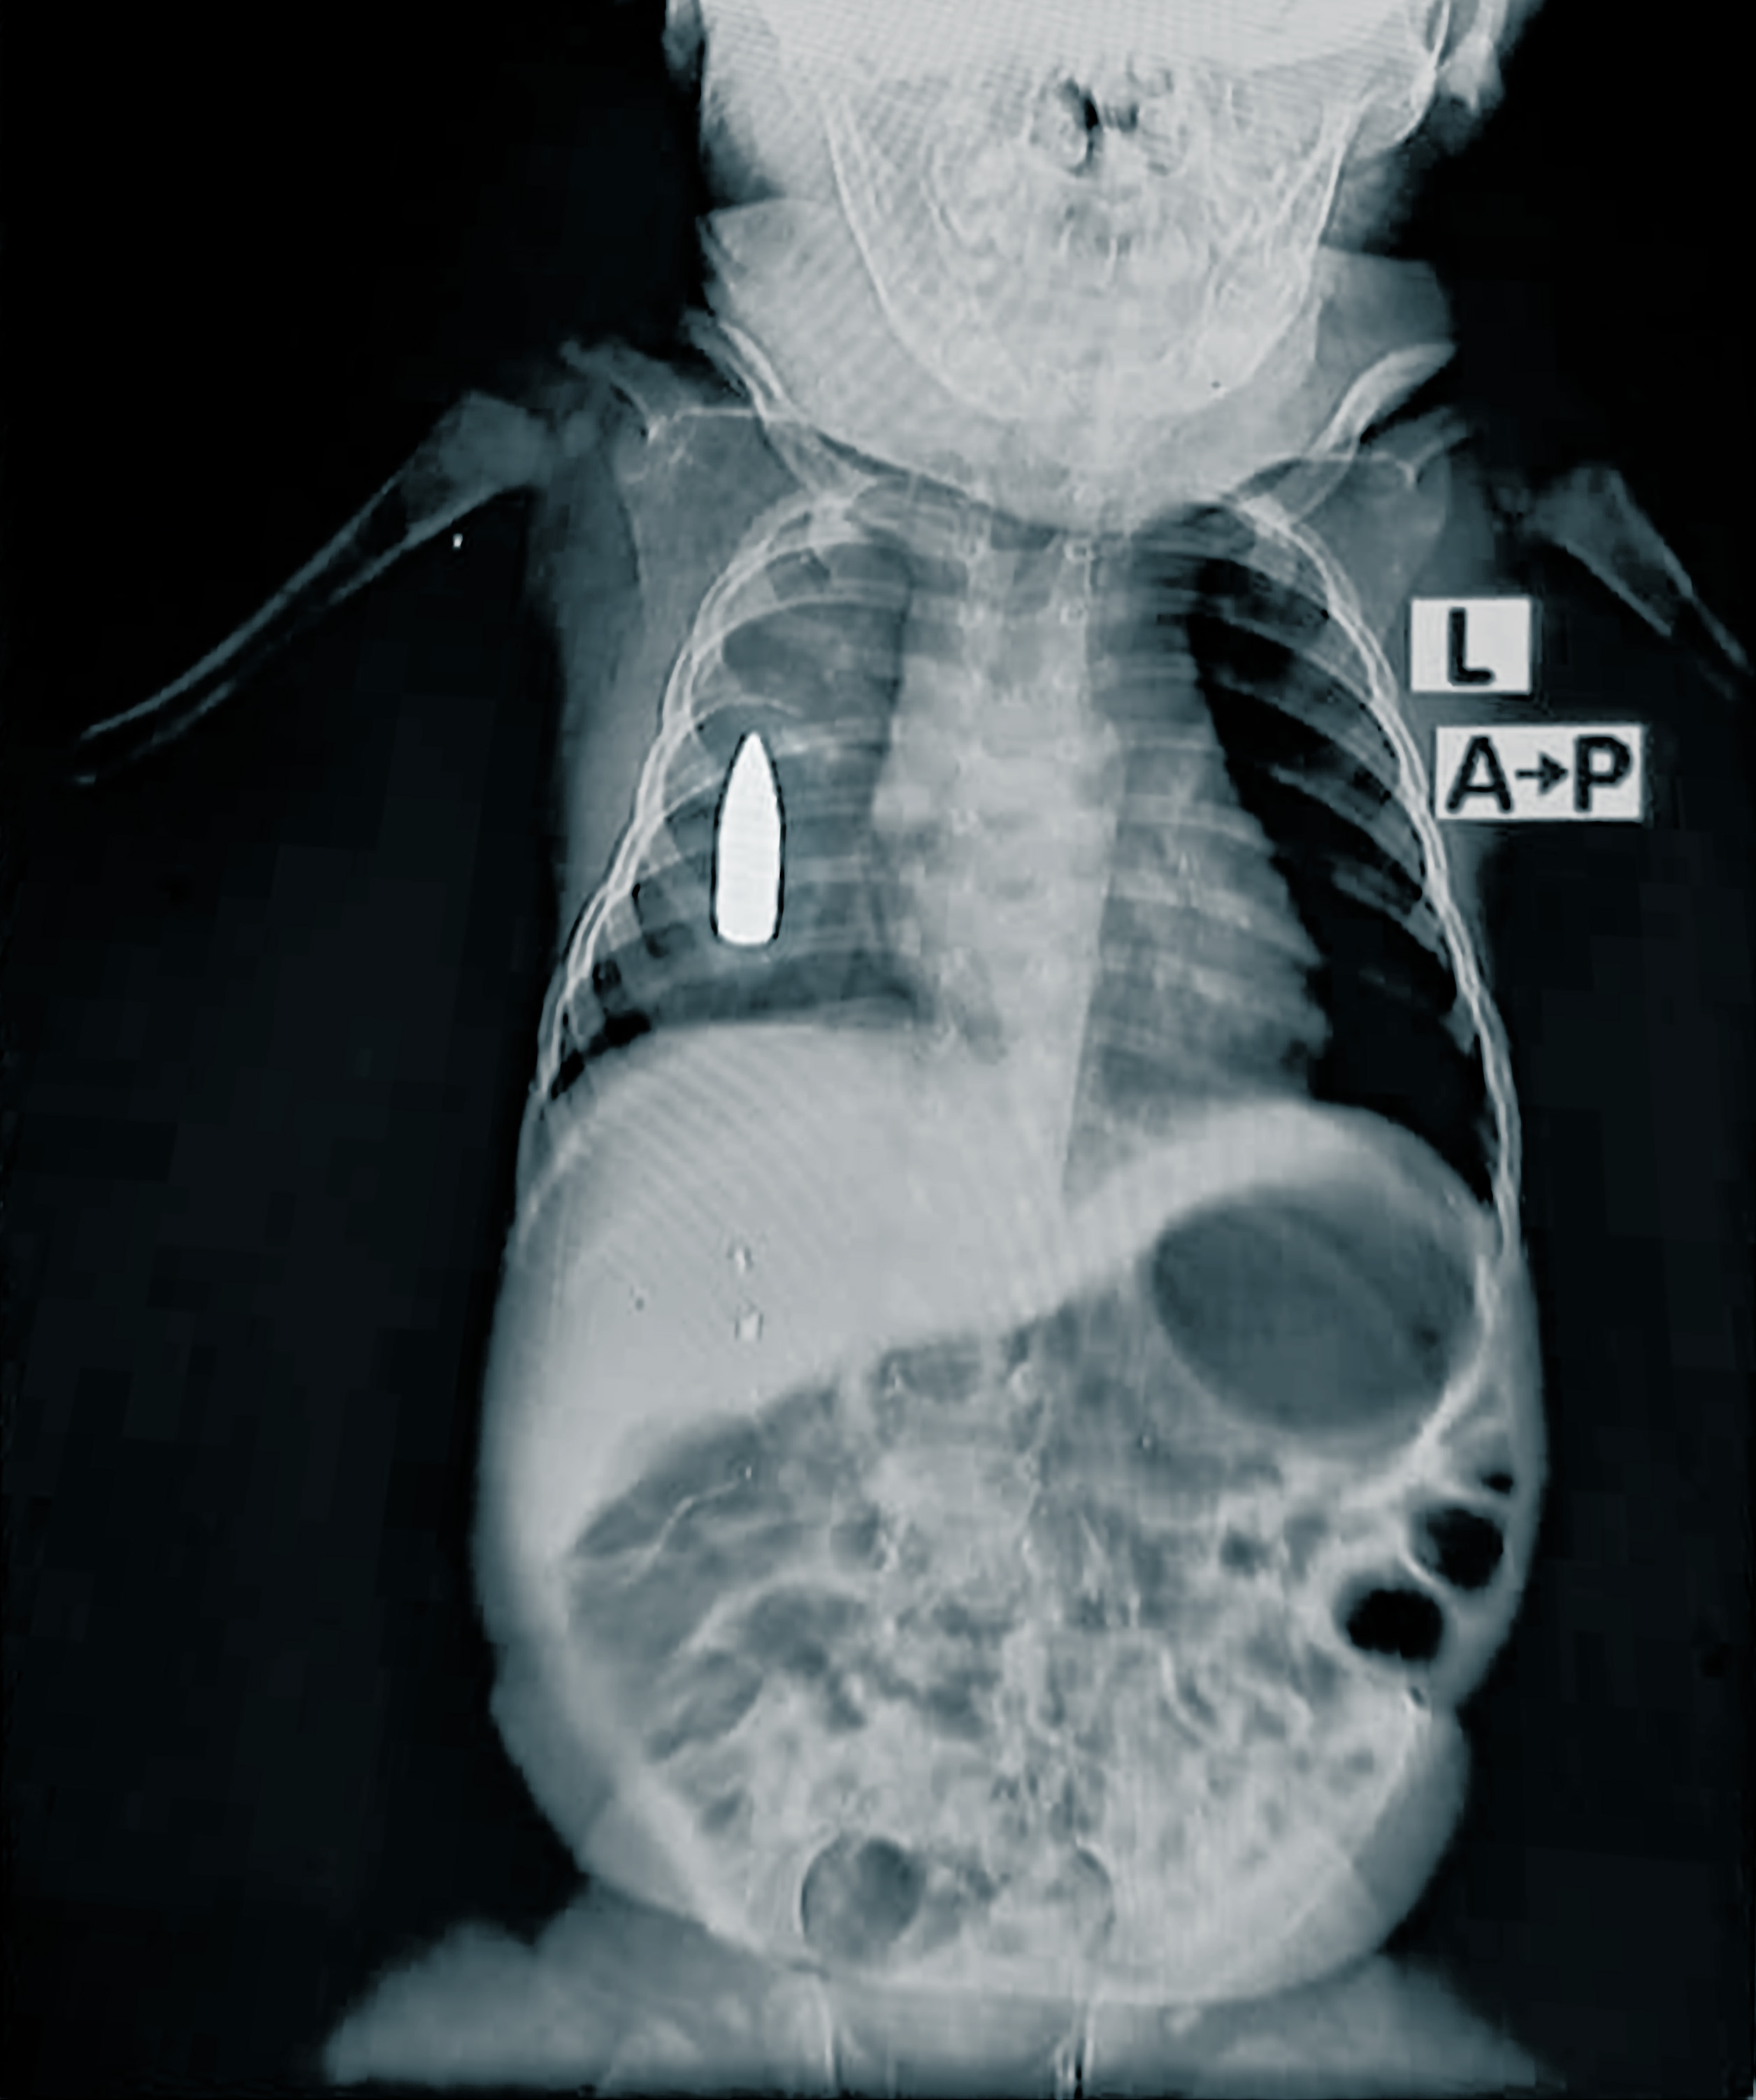

– Det 18 månader gamla pojken Riyad kom till akuten efter att han hade träffats av en förlupen kula när han sov hemma hos familjen, säger läkaren Moeen*, medicinskt ansvarig på Läkare Utan Gränser. Teamet kämpade i fyra timmar med att rädda livet på det lilla pojken. På grund av den stora blodförlusten hade han bara 50 procents chans att överleva operationen.

De lyckades stoppa blödningen men kulan sitter fortfarande kvar i bröstet. Det är oklart hur lång tid det tar innan kulan kan tas bort. Sjukhuset har inte avancerad kirurgisk kapacitet, delvis på grund av att transporter med kirurgisk utrustning systematisk har blockerats sedan oktober 2023. Att hänvisa patienter till ett annat sjukhus är också mycket svårt eftersom vägarna antingen är förstörda eller alldeles för farliga.